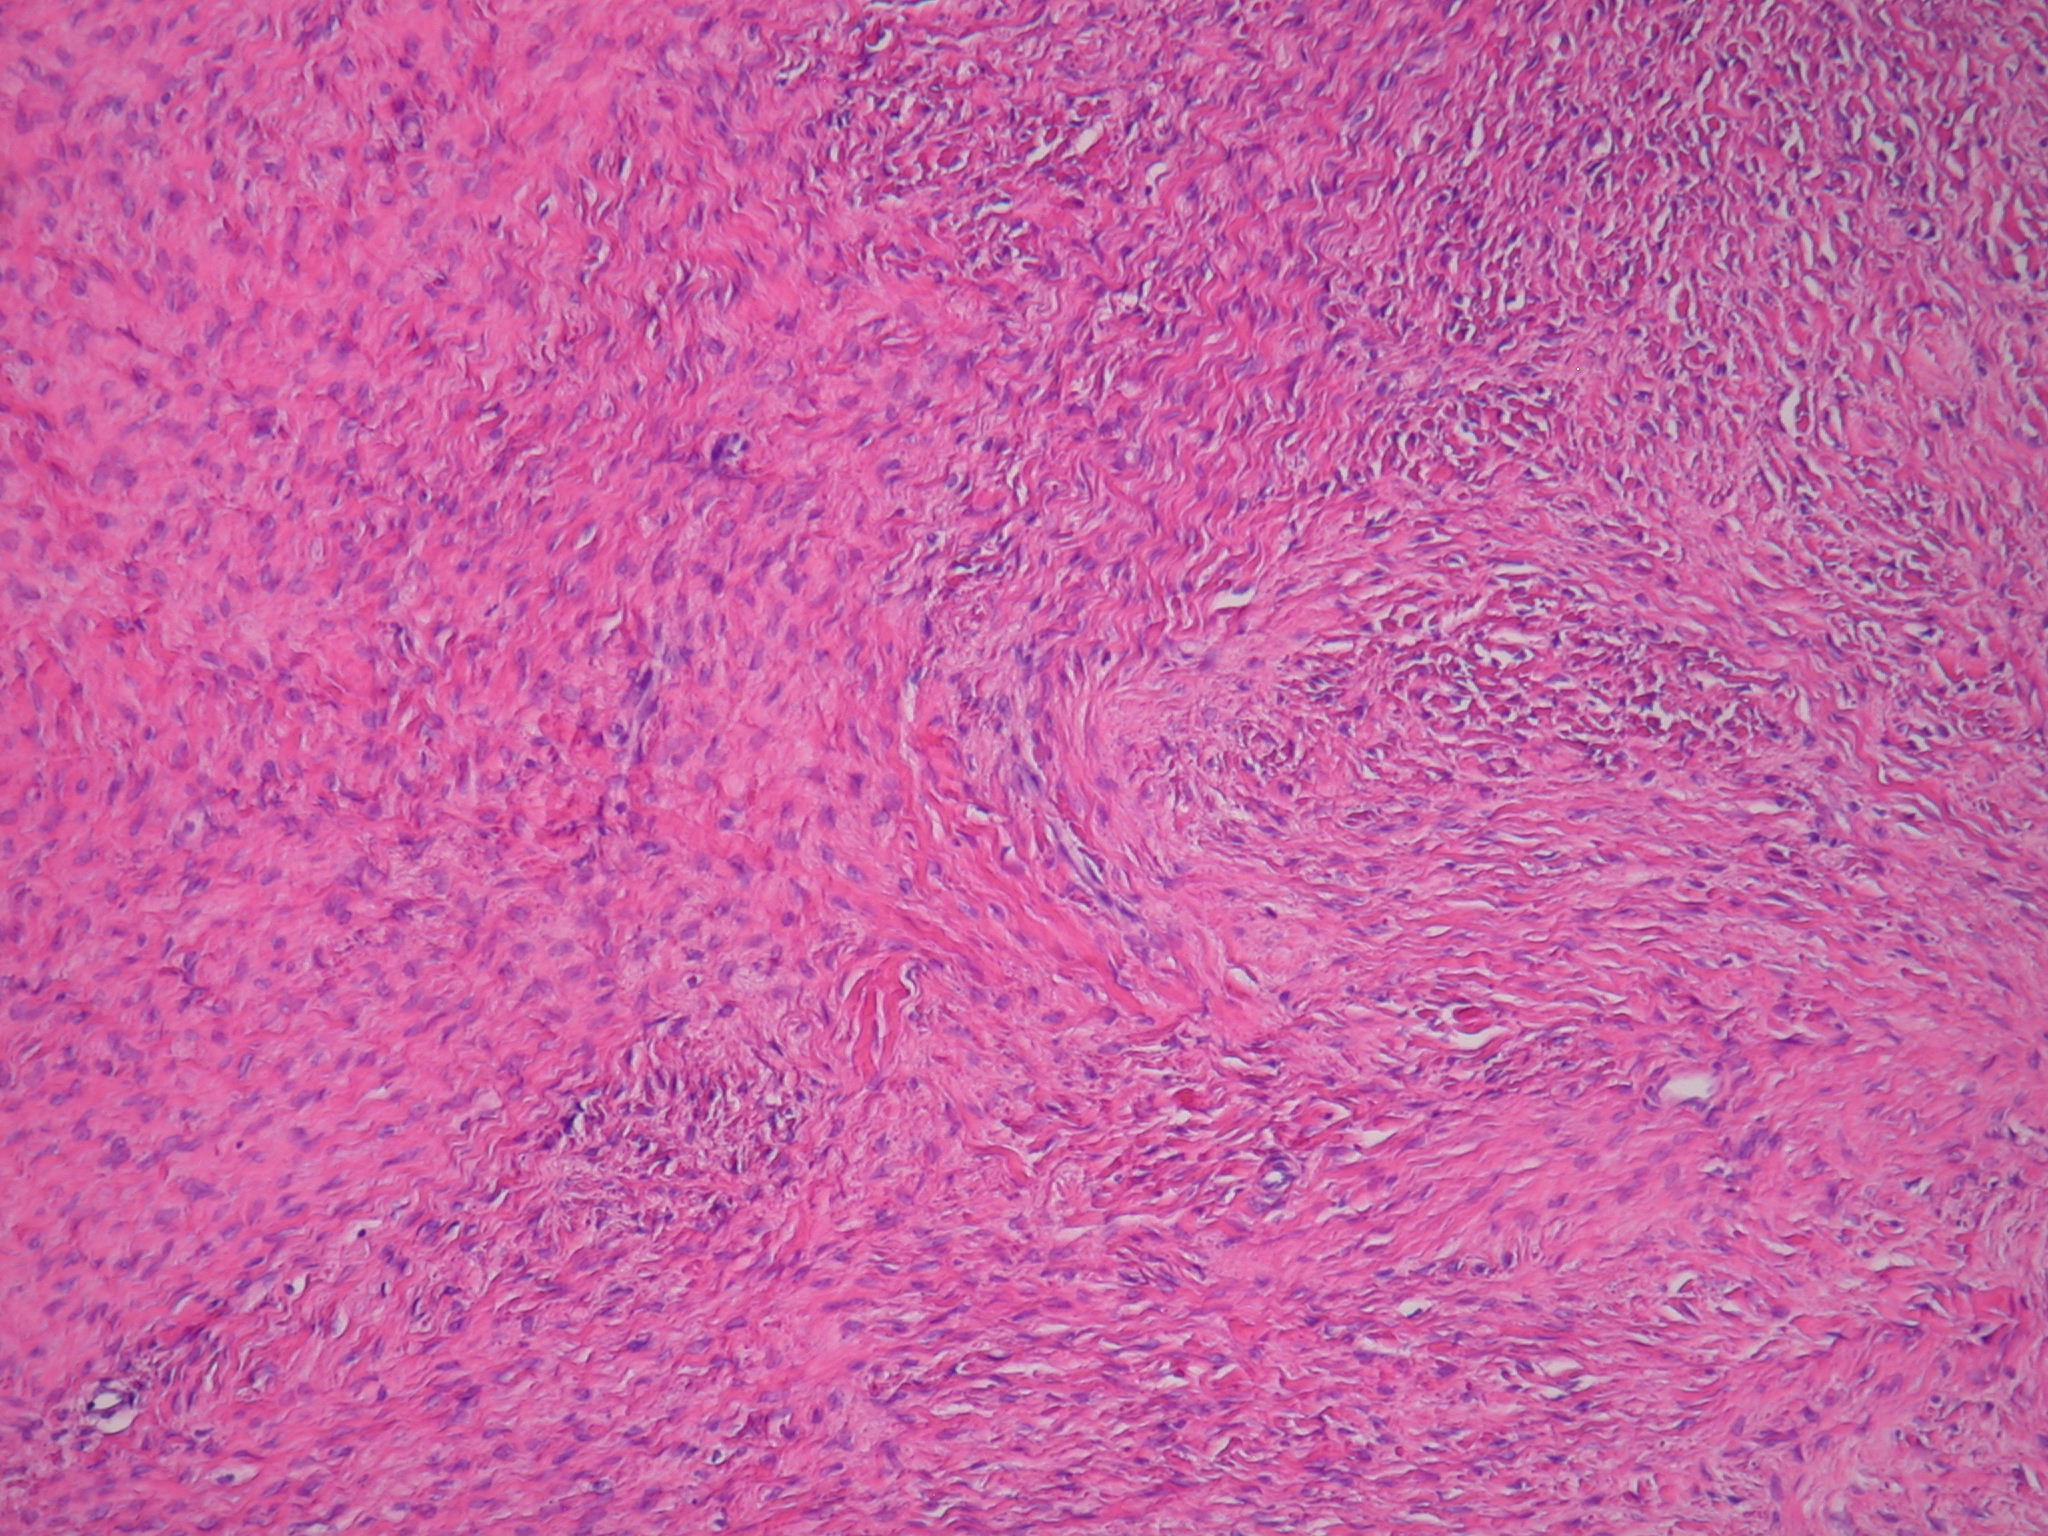

In other cases of chronic ovarian torsion, an ovarian mass or cystic structure is often found.3-5 Our patient was found to have an ovarian fibroma, a benign fibroblast tumor arising in the ovarian stroma.7 Fibromas are relatively common, accounting for 80% of sex cord-stromal tumors6 and 4% of all ovarian neoplasms.7 Grossly, ovarian fibromas often appear as firm, round, gray-white masses.7 Microscopic evaluation classically shows uniformly distributed spindle-shaped cells in a swirling pattern, with no cytologic atypia and minimal mitotic activity.6 Our patient’s mass was consistent with these findings (Figures 1 and 2).

Figure 2. Medium-power view of the ovarian mass specimen showing uniformly distributed spindle-shaped cells in a swirling pattern.